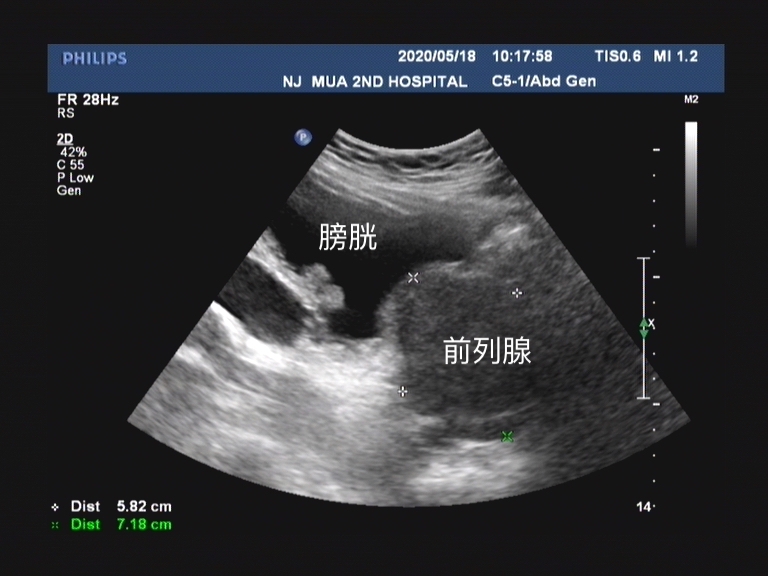

前列腺增生之所以会引起患者的排尿问题, 一方面是因为前列腺增生的腺体导致后尿道的狭窄、变细,提高了尿道的阻力。 但还有很重要的 一方面就是膀胱颈部的α肾上腺素能受体兴奋也会导致后尿道平滑肌收缩,同样也会造成膀胱出口梗阻!

α受体阻滞剂的作用机制就是 通过阻滞分布在前列腺和膀胱颈部平滑肌表面的肾上腺素能受体,松弛平滑肌,达到缓解膀胱出口动力性梗阻的作用,同时可以缓解储尿期的膀胱刺激症状。